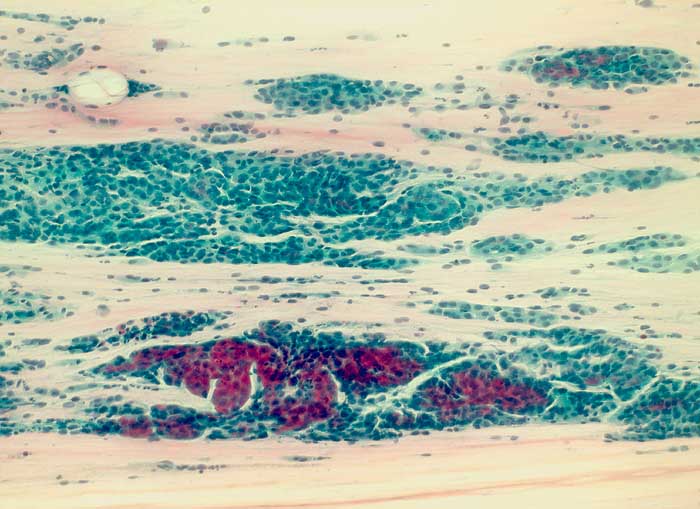

Seröses Adenokarzinom des Endometrium

Die Zellkerne der serösen Adenokarzinome sind in den meisten Fällen hochgradig atypisch. Das Zellbild gleicht entsprechend demjenigen eines wenig differenzierten endometrioiden Adenokarzinoms. Da das seröse Karzinom anders als das endometrioide Karzinom nicht Folge eines Hyperöstrogenismus ist, zeigen die meist postmenopausalen Patientinnen keinen hohen Aufbau des Vaginalepithels im PC-Abstrich.